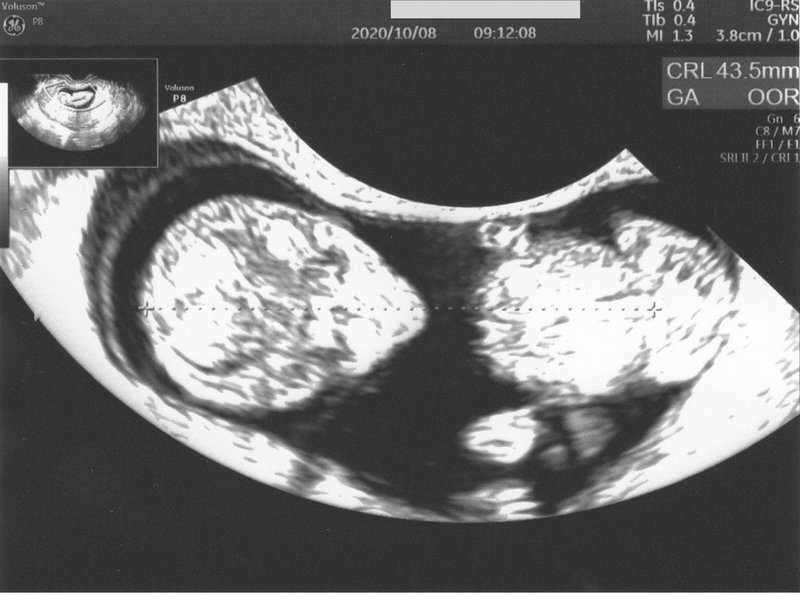

Mar 22, 17 · 妊娠9週目の「母親の体」と「赤ちゃん」の様子について解説します。母体における乳房や子宮の変化、赤ちゃんの発達状況について紹介するとともに、妊産婦の時期に必要なカルシウムの摂取方法についても紹介します。妊娠9週とは?妊娠9週目とは「妊娠63日Nov 10, · 「9週の壁」が怖かった:妊娠7w〜9w日記 なっているのも、手足がふいふい動いているのも、心拍も確認できたので安心しました。赤ちゃん239mm、心拍168bpmです。子育てママを応援する 「balloon 赤ちゃん保健室」, Kani 306 likes · 14 talking about this 岐阜県可児*美濃加茂市で開催しているベビーマッサージ教室です。アットホームな雰囲気のレッスンとお母さん達に人気!現役保健師によるレッスンです。

9週の壁 が怖かった 妊娠7w 9w日記 Akatsuki174 Note